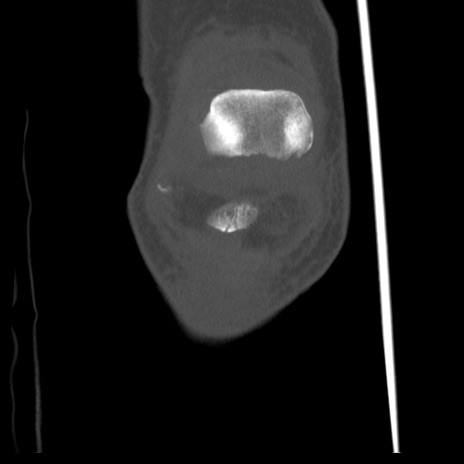

右膝関節CT

横断像